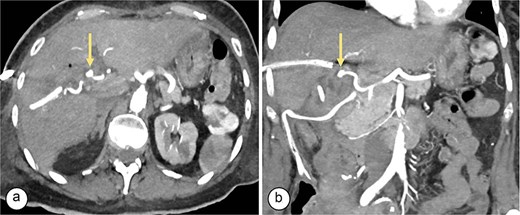

Surgical reconstruction revealed an excluded PRHD and ARHD–LHD continuity with obstruction 10 mm from the confluence. The PRHD catheter was found outside the biliary tract, so a transhepatic Nelaton catheter was placed from inside to out. A neoconfluence of PRHD with ARHD and LHD was created with a 30 mm hepaticojejunostomy. A transanastomotic Nelaton catheter and a supranastomotic ARHD catheter were left in place. Estimated blood loss: 300 cc. In the immediate postoperative period, the patient developed melena and bleeding from the Penrose drain. Cholangiography via the right percutaneous catheter showed no contrast leakage. Angio-CT revealed an 8 × 5 mm saccular lesion in the anterior right hepatic artery (Segment V), consistent with a pseudoaneurysm (Figs 1 and 2). Selective embolization with three microcoils (2 × 3 × 2.3 mm) was successfully performed (Fig. 3). The patient had a favorable recovery, with no further bleeding, and was discharged in stable condition for outpatient follow-up. Control imaging of the ARHD catheter confirmed adequate visualization of all hepatic ducts, allowing catheter removal (Fig. 4).

Angiotomography. (a) Axial slice showing a saccular image (arrow) with an aneurysmal appearance, 8 × 5 mm in size, originating from the right hepatic artery (Segment V), with no evidence of active bleeding. (b) Coronal slice showing a pseudoaneurysm (arrow) in the branch of the right hepatic artery (Segment V).